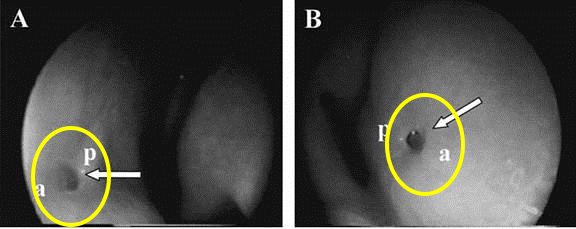

人類費洛蒙的接受器官-犁鼻器

下圖中的小孔是以內視鏡拍攝位於鼻子內的犁鼻器

人類費洛蒙接收器官-犁鼻器內視鏡圖